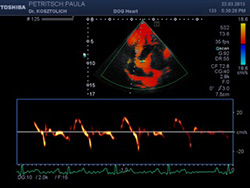

Neben der konventionellen Echokardiographie arbeiten wir mit unserem high-end Ultraschallsystem Toshiba ARTIDA. Dieses Ultraschallsystem verfügt neben den "klassischen" Ultraschallverfahren (M-Mode, zweidimensionaler Ultraschall, Spektraldoppler und Farbdoppler) über neueste Methoden der Echokardiographie:

Analyse des Herzmuskels mittels Gewebedoppler.